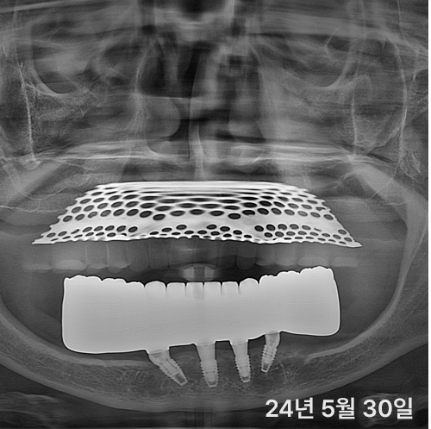

티타늄 바 케이스 (책에서 인용)

실제 환자분들의 깨끗한 통지르코니아 잇몸 반응

티타늄바는 꼭 필요한 경우에만 권해드립니다.환자분의 비용 부담을 줄이기 위해서입니다.

3년 내 보철이 깨지면 무상으로 다시 제작해드립니다. (필요시 티타늄바 넣어서)

원칙 지켜서 잘 만들면 지르코니아로 충분해요